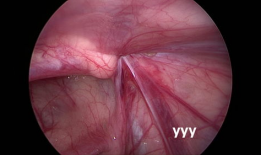

疝气手术视频,从术前准备到术后恢复

你有没有想过,当你在网上搜索“疝气手术视频”时,会出现什么样的画面呢?今天,就让我带你一起揭开这个神秘的面纱,看看那些让人既好奇...